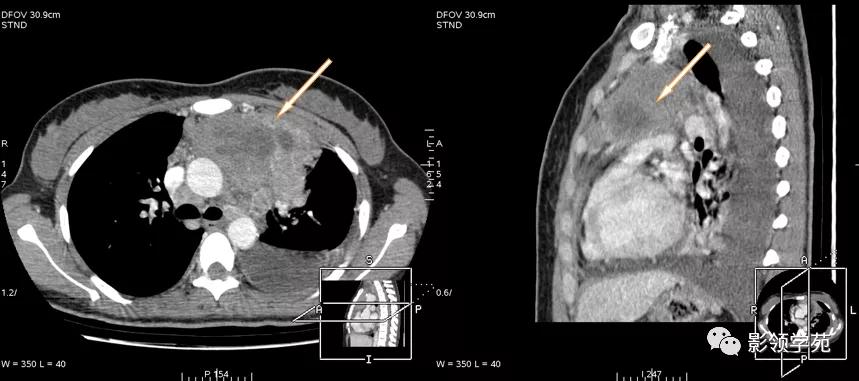

恶性胸腺瘤

穿刺证实恶性胸腺瘤,伴有纵隔淋巴结肿大